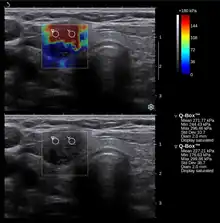

Échographie conventionnelle (en bas) et élastographie (échographie supersoniqe; en haut) d'un cancer thyroïdien papillaire. Le cancer (rouge) est beaucoup plus rigide que le tissu sain.